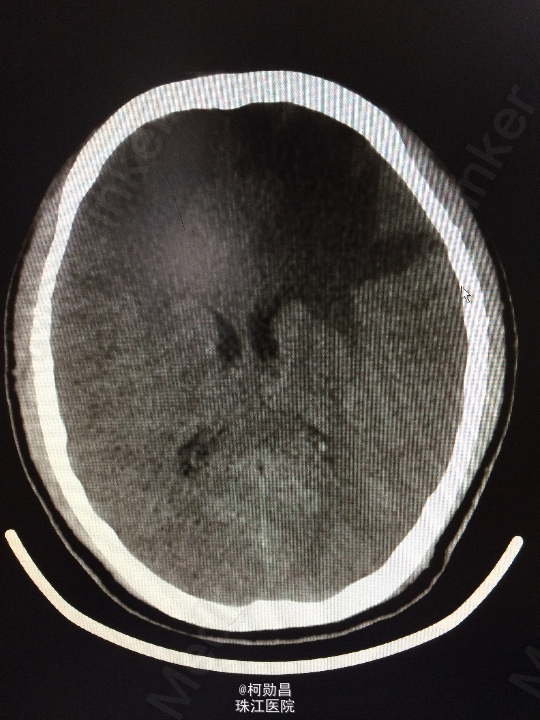

主诉:头痛伴左眼视力下降半年 病史:患者46岁男性,缘于半年前无明显诱因出现头痛,当时未予特殊处理,后症状进行性加重,并发左眼视力下降,于当地医院行头颅CT及MR检查提示颅内占位,为进一步治疗而入我院。 既往病史:5年前曾患鼻咽癌

查体:神志清楚,对答流利,左侧眼裂变小,左侧瞳孔散大,直径4mm,对光反射迟钝,左眼视力下降。右侧正常。 辅助检查:头颅MR提示前颅底筛沟通病变

诊断:鼻咽癌脑转移 处理:全麻下行颅筛沟通占位切除术,术后病理提示:鼻咽非角化鼻咽癌脑转移